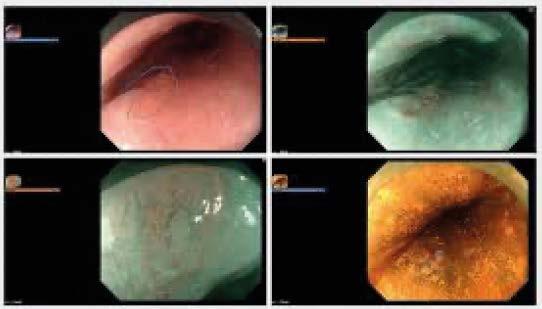

• Úlcera o masa visible en la amígdala.

Examen físico de la boca. Nasofaringoscopia.

Estudios de imagen: tomografía, resonancia magnética, PET scan,

Ultrasonido cervical con biopsia por aspiración con aguja fina.

Pruebas para el Virus del Papiloma Humano.

El tratamiento del carcinoma de gdalas incluye:

Carcinoma escamoso no queratinizante (asociado a VPH): 60–70 %.

• Carcinoma escamoso queratinizante: 20–30 %.

• Carcinoma indiferenciado: 5 %.

• Linfoma no Hodgkin: 1–3 %.

• Melanoma primario de amígdala (muy raro).

El método a utilizar dependerá del momento del diagnóstico (temprano o tardío), del tipo histológico y del tamaño del tumor, entre otros factores.